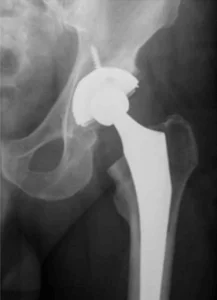

A substituição da articulação por uma prótese, que muitas vezes é a única solução para aliviar as dores nos estágios mais graves da artrose, tem aumentado nas últimas décadas.

Entretanto, nos pacientes com artrose de grau leve a moderado, ou naqueles que possuem alguma contraindicação para a realização do procedimento cirúrgico, existem algumas medidas que ajudam no controle da dor que inclui o uso de analgésico, antiinflamatório não esteroides, fisioterapia, injeções de corticóides intra-articulares e a viscossuplementação.